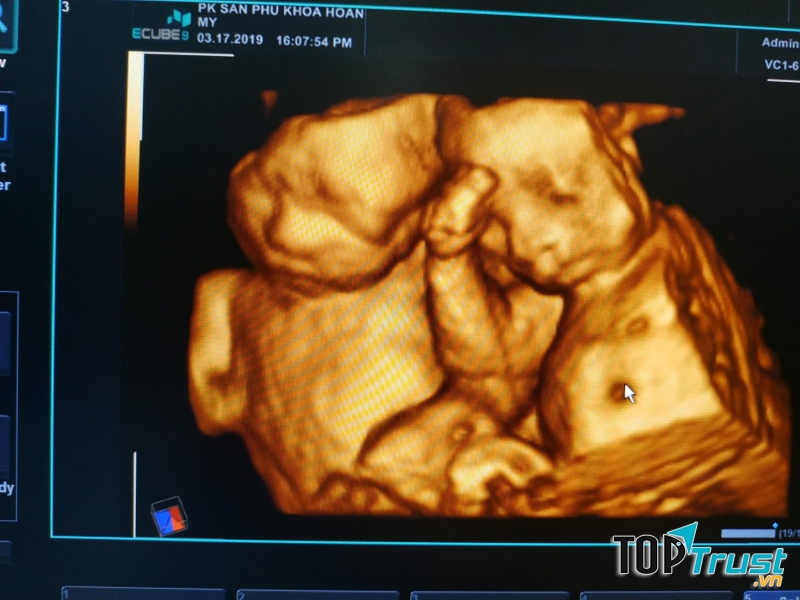

Phòng Khám Sản Phụ Khoa Hoàn Mỹ

Phòng Khám Sản Phụ Khoa Hoàn Mỹ là một trong những phòng khám quen thuộc của các mẹ mang thai ở Vĩnh Phúc. Có thể nói đây là 1 phòng khám được đánh giá là kiểm tra thai nhi tốt, uy tín, siêu âm kỹ càng tạo cảm giác thoải mái, tận tình với từng người đến khám, với kinh nghiệm lâu năm trong nghề.

Các dịch vụ của Phòng Khám Sản Phụ Khoa Hoàn Mỹ bao gồm:

- Khám thai định kỳ

- Siêu âm chuẩn đoán thai

- Khám phụ khoa và các vấn đề khác liên quan đến sản phụ khoa